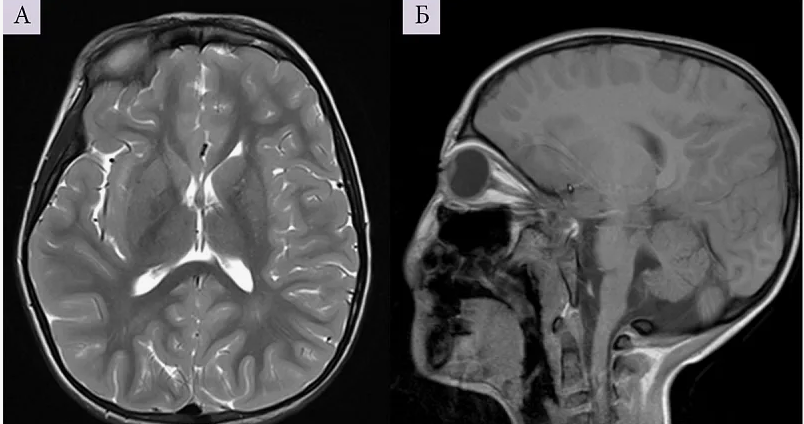

Магнитно-резонансная томография (МРТ):один из самых эффективных методов диагностики заболеваний